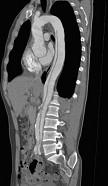

问题 请看一组主动脉的CT增强图像,正确的描述和结论是 ( )

选项 A、真腔较假腔小 B、真假腔之间线状低密度影为内膜片影 C、主动脉瘤 D、主动脉夹层 E、主动脉血栓 一、多项选择题

答案 ABD